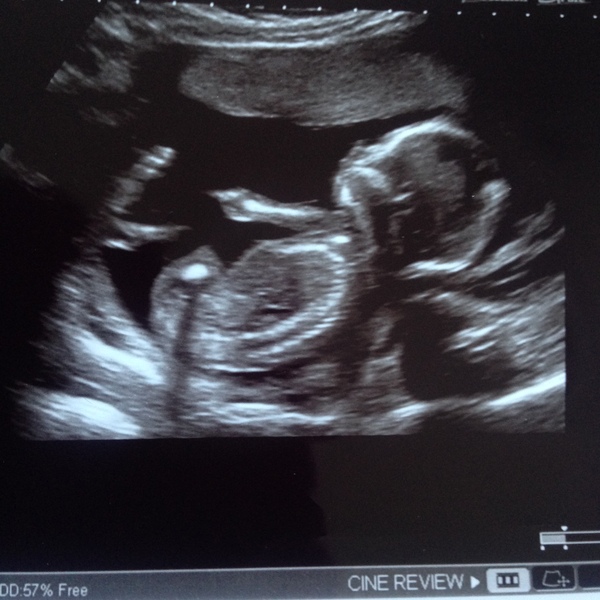

Can anyone guess girl or boy at 16 weeks? :)

Can't see any detail of the bits that matter but my instinct says boy!

I would say boy. I have no idea though

Girl I think. 😊

Looks very girly to me but couldn't tell you why! Good luck Flowers

I think boy only because it looks similar to my first boys scan x